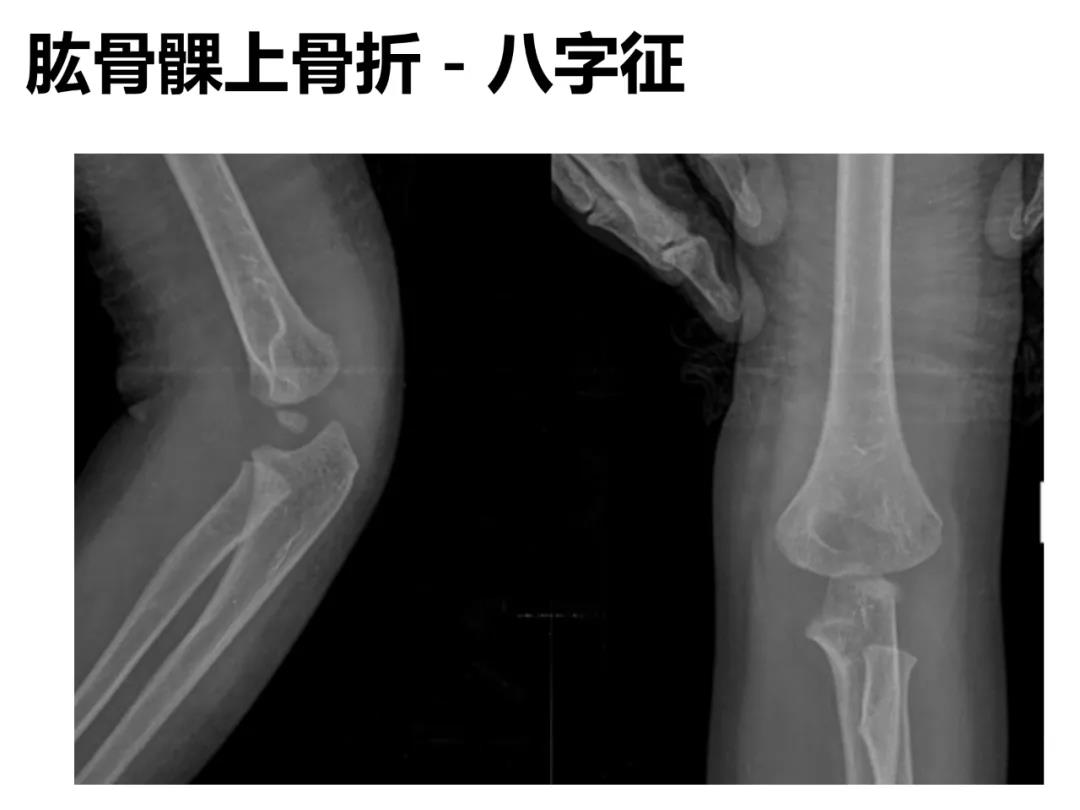

小儿骨科X线片汇总,临床读片宝典!